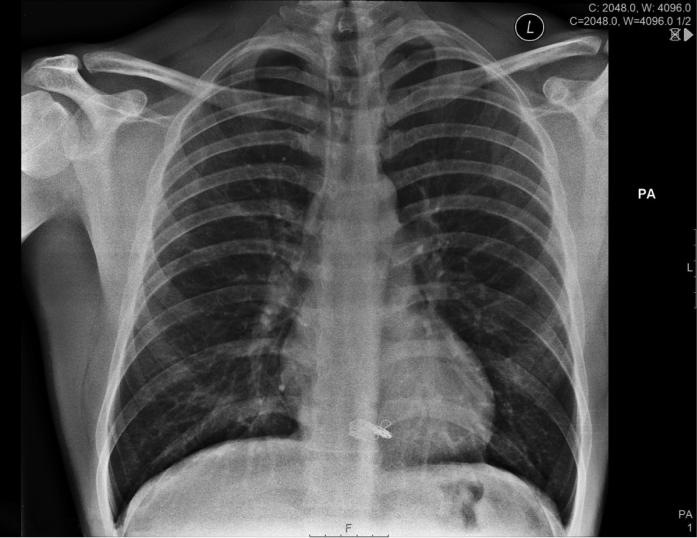

We describe a case of an adult patient with embolization of a varicocele coil (7 × 70 mm) to the right ventricle. We review the multimodality imaging techniques used to identify location and the importance of a multidisciplinary approach in determining management. ().

我们描述了一例成年患者,其精索静脉曲张线圈(7×70毫米)栓塞至右心室。我们回顾了用于确定位置的多模态成像技术以及多学科方法在确定治疗方案中的重要性。()